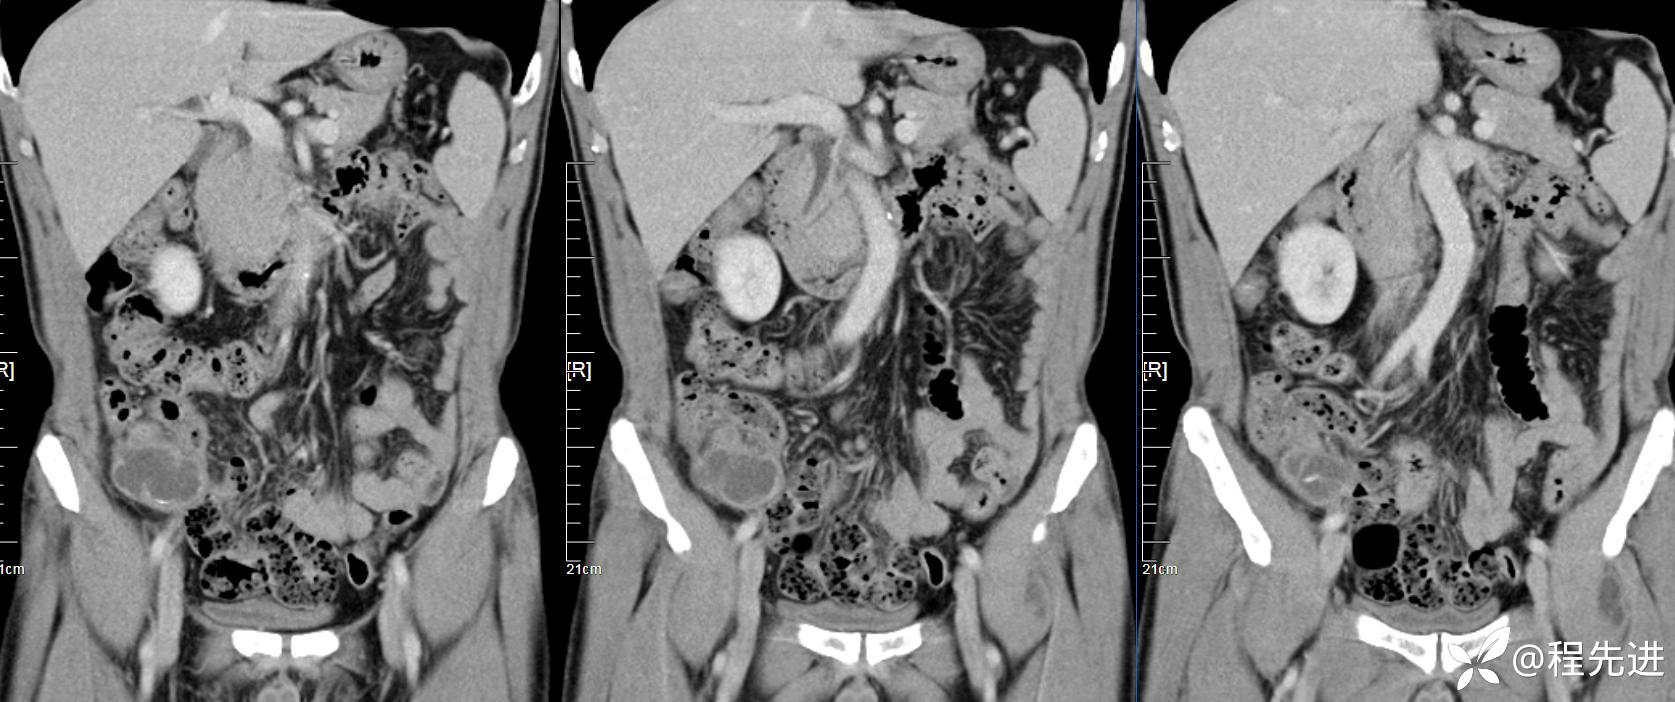

【患者信息】:男,61岁

【现病史及既往史】:右下腹部疼痛伴腹胀2天

【影像检查】